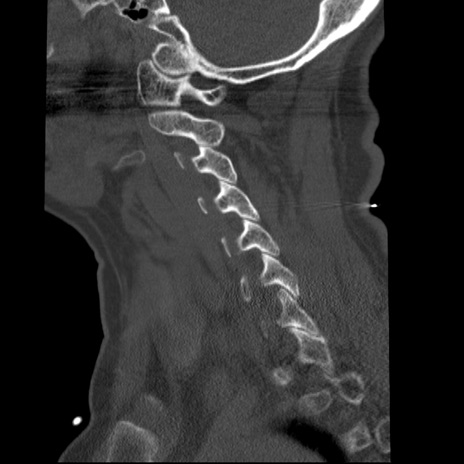

症例50 頚椎CT(矢状断像)

【症例】60歳代女性

【主訴】後頭部〜右後頸部にかけての痛み

【現病歴】本日飲食店でコーヒーを飲んでいたところ、突然後頭部〜右後頸部にかけて痛みが出現し、右上肢の感覚障害を伴ったため救急要請。

【身体所見】脳神経学的に明らかな異常所見を認めず。右上肢に軽度の感覚障害あり。

異常所見と診断は?

冠状断像